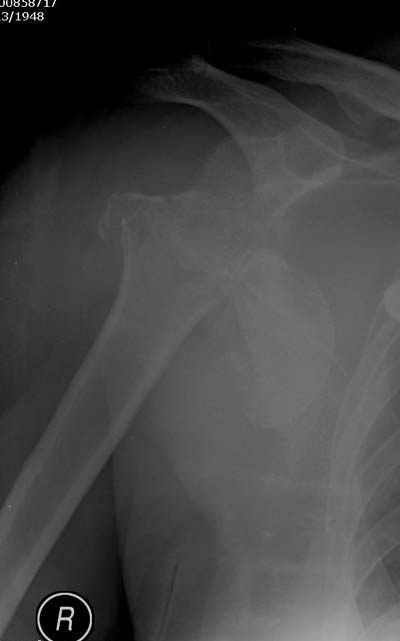

Здесь случай перелома-вывиха плеча, больному 56 лет, после "дважды" закрытой неудачной репозиции, опять же ургентно взяли в операционную, после полного общего обезболивания попытались сделать репозицию, и фиксацию провели спицами.

Больной находился в повязке, примерно напоминяющей косыночную, рекомендованы движения в локтевом суставе и маятниковые движения в плече, спицы удалены в три недели (были случаи миграции)

Больной амбулаторный, предупрежден на случай осложнения АВН головки.

Клинические снимки - 3 недели после операции